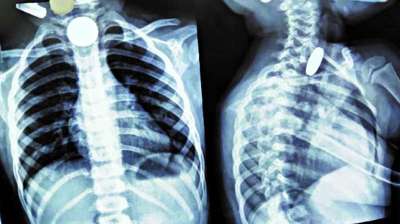

खेलते-खेलते बच्चे ने निगल लिए सिक्के, खाने की नली में फंसे; डॉक्टरों की टीम ने ऐसे बचाई जान

दिल्ली : दिल्ली के एक सरकारी अस्पताल के डॉक्टरों ने 12 वर्षीय बच्चे की जान बचाई है। बच्चे ने पांच और दस रुपये के तीन सिक्के निगल लिए थे। सिक्के...